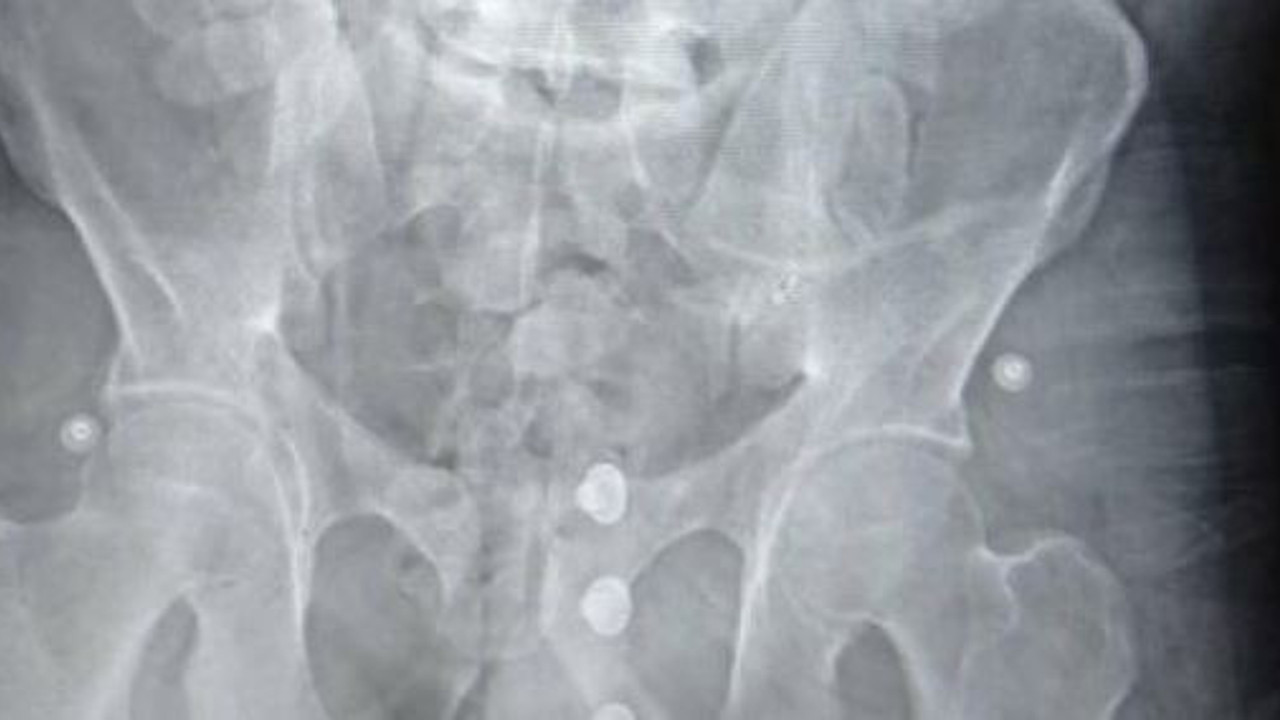

Tomografi cihazı ile gerçekleştirilen iç beden görüntüleme muayenesinde mide ve bağırsaklarında çok sayıda kapsül olduğu tespit edildi. Şüphelinin sağlık durumu da göz önünde bulundurularak 3 gün hastanede tutuldu.

Tıbbi gözlem süreci boyuncu sürdürülen çalışmalar neticesinde zanlının mide ve sindirim sisteminde bulunan 155 adet kapsül reçine esrar daha çıkarıldı. Fas’ta yutarak midesine yerleştirdiği 194 kapsül halindeki 1 kilo 545 gram reçine esrarı Türkiye’ye getiren zanlı sevk edildiği mahkemece tutuklanarak cezaevine gönderildi.